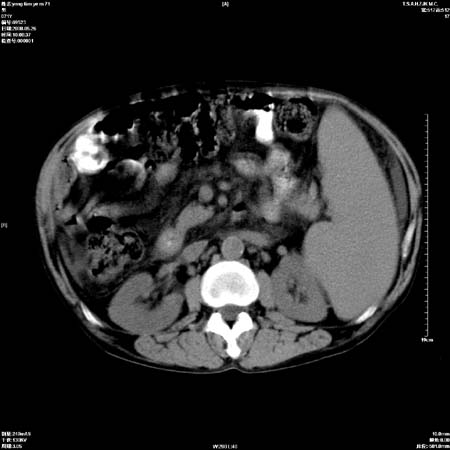

以下是引用医影拾贝在2008-6-5 22:48:00的发言:[br]肝硬化、门脉高压、胃底食管静脉曲张、低蛋白血症(胆囊壁水肿、增厚)、腹水[br]脾功能亢进、脾大、脾、左肾囊肿[br]肝囊性占位、不除外肝脓肿可能[br]建议增强以除外肝右叶肝ca可能

以下是引用chenglinhunan在2008-6-5 22:53:00的发言:[br]1. 肝硬化腹水,脾肿大。[br]2. 肝右后叶占位,肝癌。[br]3。建议ct增强扫描。

以下是引用xulianj在2008-6-5 21:40:00的发言:[br]支持肝硬化腹水;建议增强。肝、脾、肾囊肿待排。

以下是引用zjzjr在2008-6-6 12:34:00的发言:[br]1. 肝硬化腹水,脾肿大。[br]2. 肝右后叶占位,肝癌。[br]3。建议ct增强扫描。[br]4肝脾囊肿.